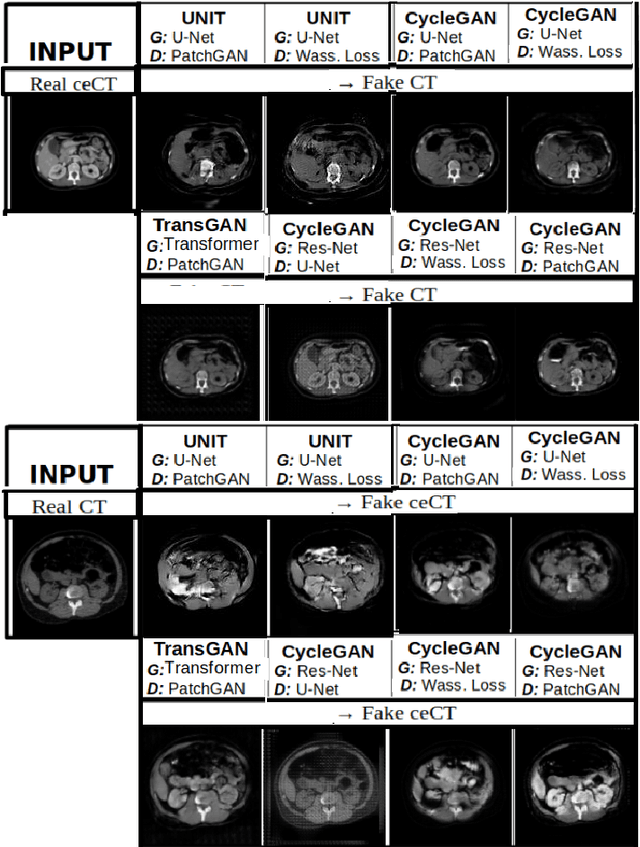

Abstract:Anatomical structures such as blood vessels in contrast-enhanced CT (ceCT) images can be challenging to segment due to the variability in contrast medium diffusion. The combined use of ceCT and contrast-free (CT) CT images can improve the segmentation performances, but at the cost of a double radiation exposure. To limit the radiation dose, generative models could be used to synthesize one modality, instead of acquiring it. The CycleGAN approach has recently attracted particular attention because it alleviates the need for paired data that are difficult to obtain. Despite the great performances demonstrated in the literature, limitations still remain when dealing with 3D volumes generated slice by slice from unpaired datasets with different fields of view. We present an extension of CycleGAN to generate high fidelity images, with good structural consistency, in this context. We leverage anatomical constraints and automatic region of interest selection by adapting the Self-Supervised Body Regressor. These constraints enforce anatomical consistency and allow feeding anatomically-paired input images to the algorithm. Results show qualitative and quantitative improvements, compared to stateof-the-art methods, on the translation task between ceCT and CT images (and vice versa).